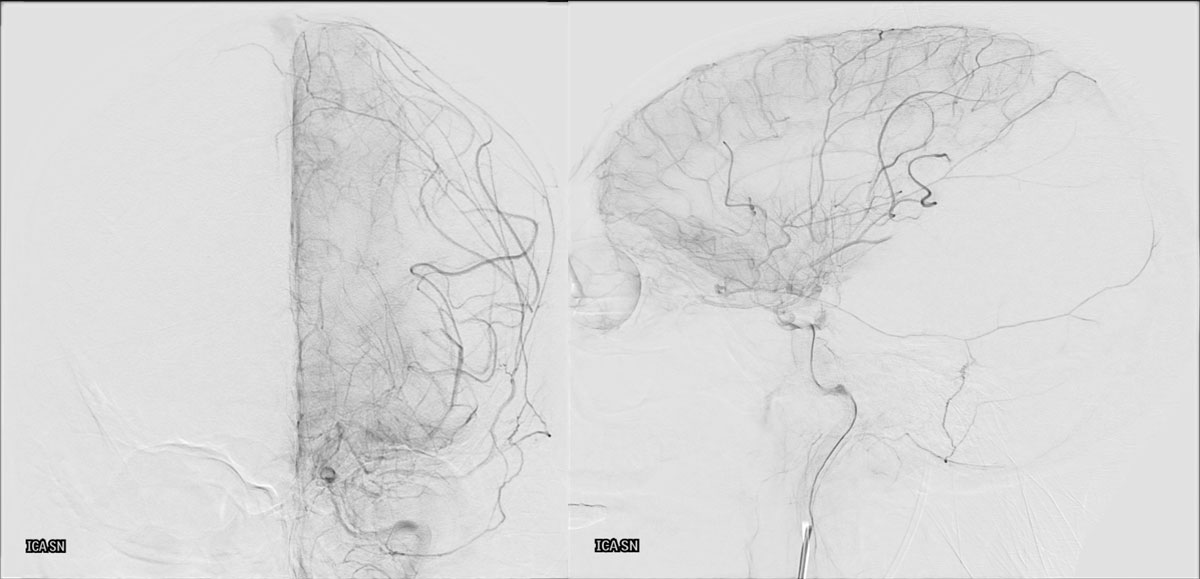

DSA

L - VERT

L - ICA